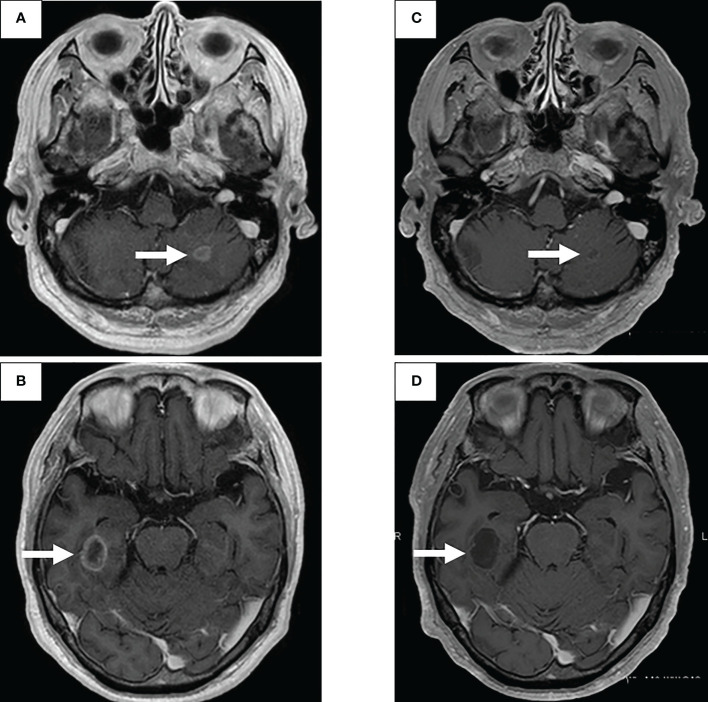

图2:使用二线治疗塞尔帕替尼的脑转移疗效

一线治疗包括卡铂+培美曲塞+贝伐单抗,经过4个疗程后获得近乎完全缓解(CR),但鼻出血仍然持续,仅进行培美曲塞维持治疗。在维持治疗的25个疗程中实现了CR(图1C),但由于肾功能轻微恶化,治疗暂时中断。治疗结束后一年,CT显示原发病灶轻微进展(图1D),但复发速度较慢。确认CT复发一年后(图1E),重新开始培美曲塞单药治疗,原发病灶和淋巴结减小(图1F)。然而,在进行了32个维持治疗疗程后,出现了快速的全身进展。由于原发病灶再生(图1G)、对侧肺转移、多发性肝转移、右侧肾上腺转移和多发性脑转移(图2A、B),需要调整他的治疗方案。

通过支气管镜对原发病灶进行再活检,细胞学评估显示V级腺癌,组织学评估证实了这一结果。肿瘤精准用药850基因检测确认患者为RET融合基因阳性,随后于第二天给予240mg塞尔帕替尼。第13天的CT显示与基线影像相比(图1H),所有转移病灶,包括脑转移(图2C、D),均有良好的全身反应。由于2级肝酶升高,继续给予剂量减少的塞尔帕替尼(每天160mg)。使用高敏感度的下一代测序(NGS)面板系统:肺癌紧凑面板,并使用细胞学刷液进行RNA检测,证实了融合基因KIF5B外显子15;RET外显子12(K15RET12)。肿瘤精准药基因解码基因检测还能够从7年前的胸腔积液细胞块的福尔马林固定石蜡包埋(FFPE)标本中进一步确认RET(图3A、B),这些标本在恶性细胞的形态学上与再活检样本相似,具有大核仁(图3C、D)。从初始细胞块样本中收集到的RNA(1256ng)具有RNA整合数(RIN)值为4.8。单重PCR和NGS检测均检测到了K15RET12融合峰(图3)。